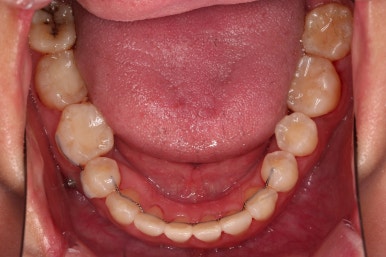

치열이 매우 가지런해졌고, 아래 앞니 사이 틈새도 점점 오므려져 가고 있습니다.

발치 공간을 적극적으로 줄여 나갑니다.

이 과정에서 입매, 앞니 각도, 정중선 등을 신경 써줍니다.

아무래도 상하좌우 비어 있는 공간의 위치가 모두 달랐기 때문에 자칫하면 중앙선이 한 쪽으로 쏠려버릴 수 있기 때문이죠.

위아래 좌우 치아가 없는 위치가 모두 달랐지만 교합도 잘 구성했고요.

아무래도 좌우 치아 크기들이 다르다 보니(뽑은 치아가 다르니) 중앙선은 100% 일직선은 안맞더라도 매우 정상 범주로 마무리를 할 수 있었습니다.

특히 어금니에 보이던 충치도 깔끔하게 마무리 했고요.